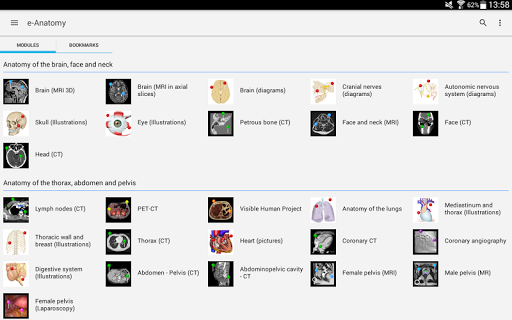

IMAIOS e-Anatomy es un atlas de anatomía humana para médicos, radiólogos, estudiantes de medicina y técnicos en radiología. Echa un vistazo a más de 26 000 imágenes médicas y anatómicas de forma gratuita antes de suscribirte a nuestro detallado atlas de anatomía humana.

e-Anatomy se basa en el galardonado atlas en línea IMAIOS e-Anatomy. Lleva contigo la referencia más completa de anatomía humana, dondequiera que vayas, en tu dispositivo móvil o tableta.

e-Anatomy tiene más de 26 000 imágenes que contienen series de imágenes en vistas axiales, coronales y sagitales, así como radiografías, angiografías, imágenes de disección, gráficos anatómicos e ilustraciones. Todas las imágenes médicas fueron etiquetadas cuidadosamente, más de 967 000 etiquetas disponibles en 12 idiomas, incluida la Terminologia Anatomica latina.

Nuevo: ahora puede filtrar los módulos por región o por tipo de contenido para que pueda encontrar el módulo que busca mucho más rápido.